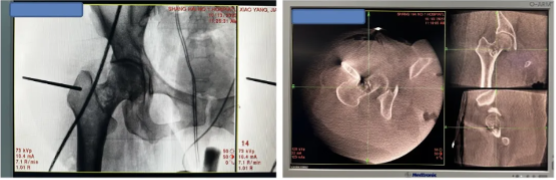

图4: 微创手术配置实时三维CT及最新美敦力S8导航

图6:导航下一次穿刺到病灶,病灶磨钻清理,孔镜通道下可视化操作